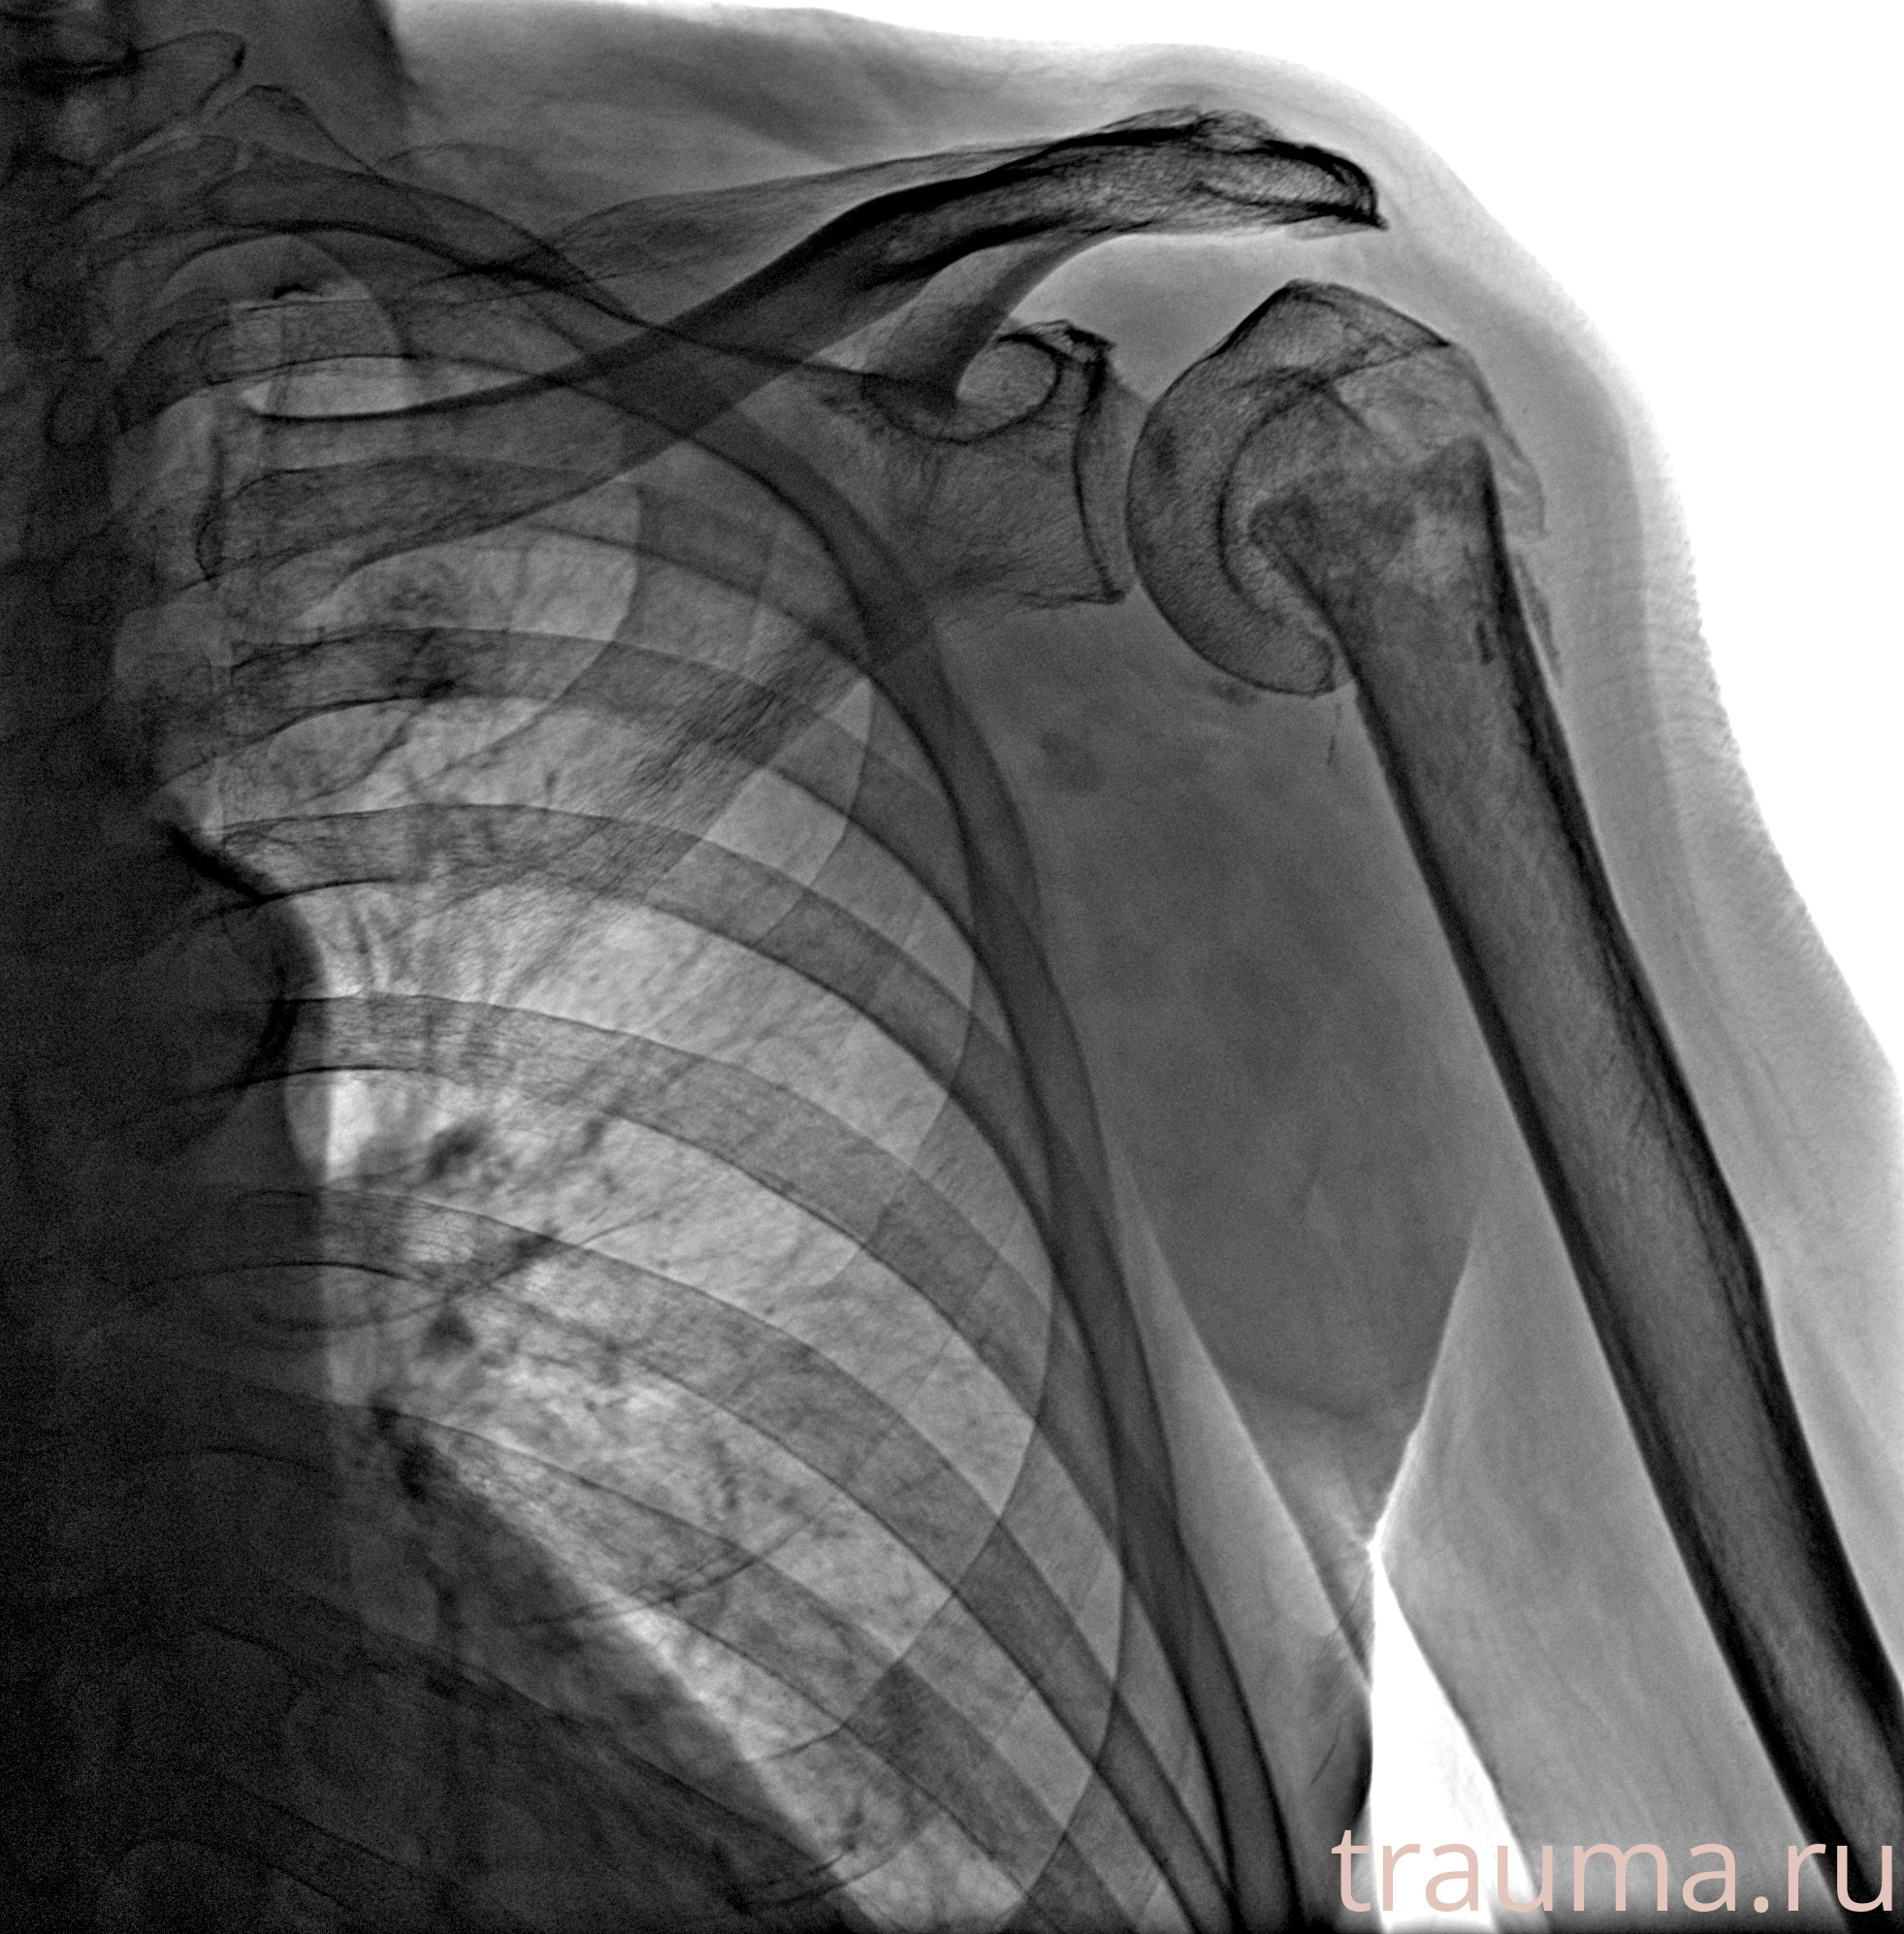

Рентгенограммы